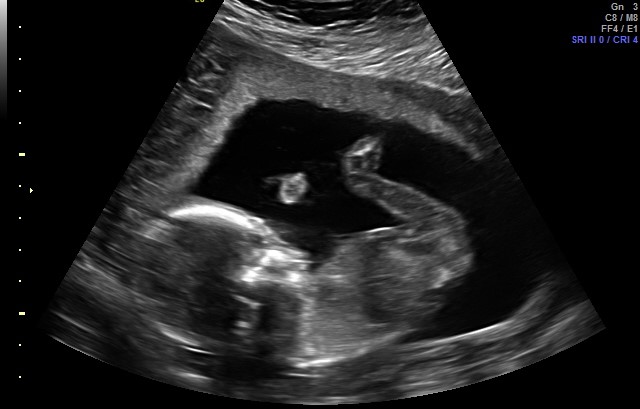

I was told a boy by this ultrasound photo, but i am having a hard time understanding the picture. Can someone help? I was sure I was having a girl, too, and this isn’t helping my confusion! https://uploads.tapatalk-cdn.com/201...d73731cca5.jpg